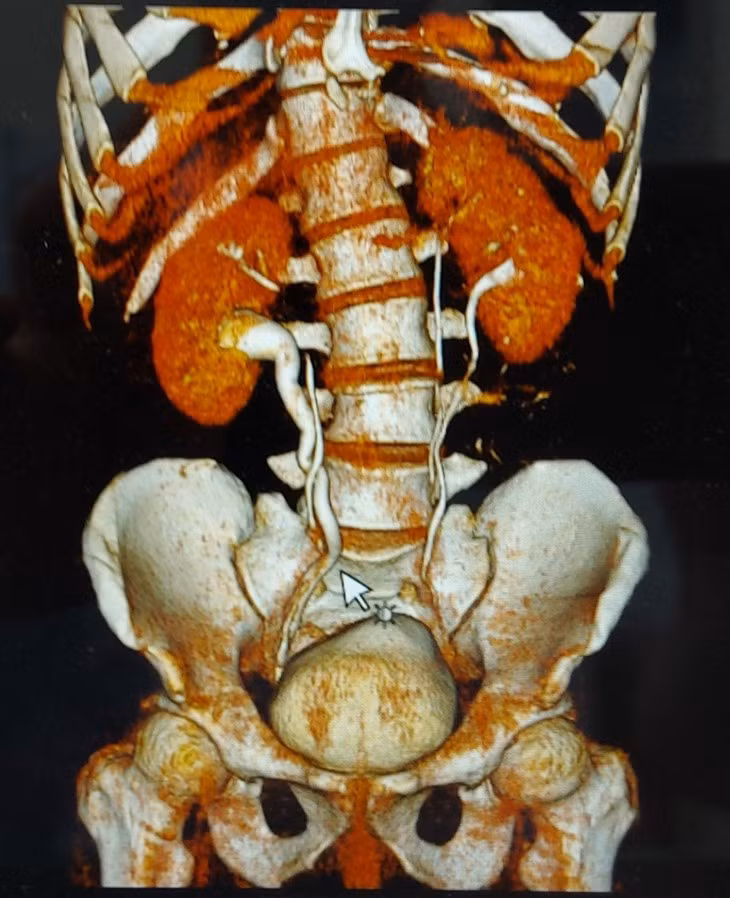

Bất ngờ hơn, kết quả chụp CT các bác sĩ phát hiện người bệnh có thận niệu quản đôi hoàn toàn hai bên trái, phải và hai niệu quản riêng biệt đều cắm xuống bàng quang. Người bệnh có bất thường về giải phẫu hệ tiết niệu, có nhiều đơn vị thận hơn bình thường là một trong những nguyên nhân hình thành sỏi thận.

Các bác sĩ đã tiến hành cắt bỏ 1 bàng quang nhỏ cho con gái khi được 18 tháng tuổi, cấu tạo lại hệ tiết niệu cho con. Đồng thời, các bác sĩ khuyên mọi người trong gia đình tầm soát hệ tiết niệu thì phát hiện anh bất thường khi có tận 4 quả thận trong cơ thể.

Đây là dị tật bẩm sinh hiếm và là do mầm niệu quản bên trái phát triển bất thường trong lúc bào thai hình thành và phát triển. Bình thường mầm niệu quản phát triển thành một quả thận và người bình thường chỉ có hai quả thận.

Tuy nhiên có một số ít người, một mầm niệu quản thay vì phát triển thành hai quả thận lại phát triển thành 4 quả thận như trường hợp của người bệnh này là cực kỳ hiếm gặp, đến nay y văn thế giới ghi nhận chưa nhiều. Rất may cho người bệnh là 4 quả thận và 2 niệu quản riêng biệt đều cắm đúng vị trí bàng quang nên loại trừ được nhiều biến chứng nguy hiểm khác trong cơ thể.